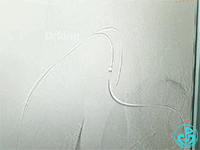

从影像上看似乎漏口在右锁骨下与右颈动脉分叉近端。

从肱动脉置入8F鞘管,送导丝至“漏口”无法到位,导丝习惯性穿行右胸肩峰动脉中,造影发现血液外溢消失,考虑穿孔口为右胸肩峰动脉远端。接下来送入三个弹簧圈。